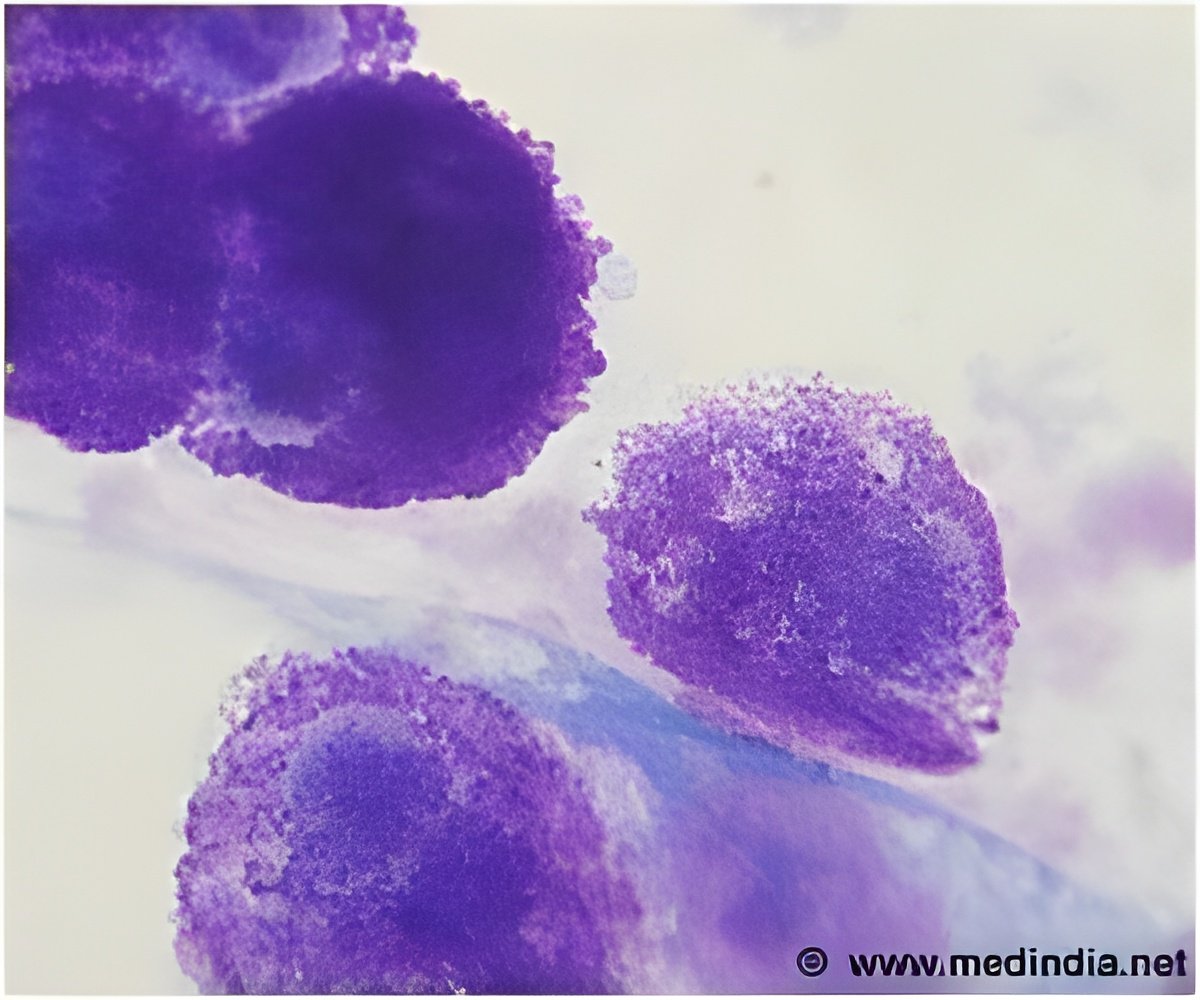

Angiogenesis is the process of generation and growth of blood vessels. It is a natural mechanism that is activated when oxygen does not reach some cells in a tissue and they secrete growth factors. When these substances reach a blood vessel, its walls open and capillaries emerge and move toward the area where the growth factors are secreted, taking oxygen and nutrients there.